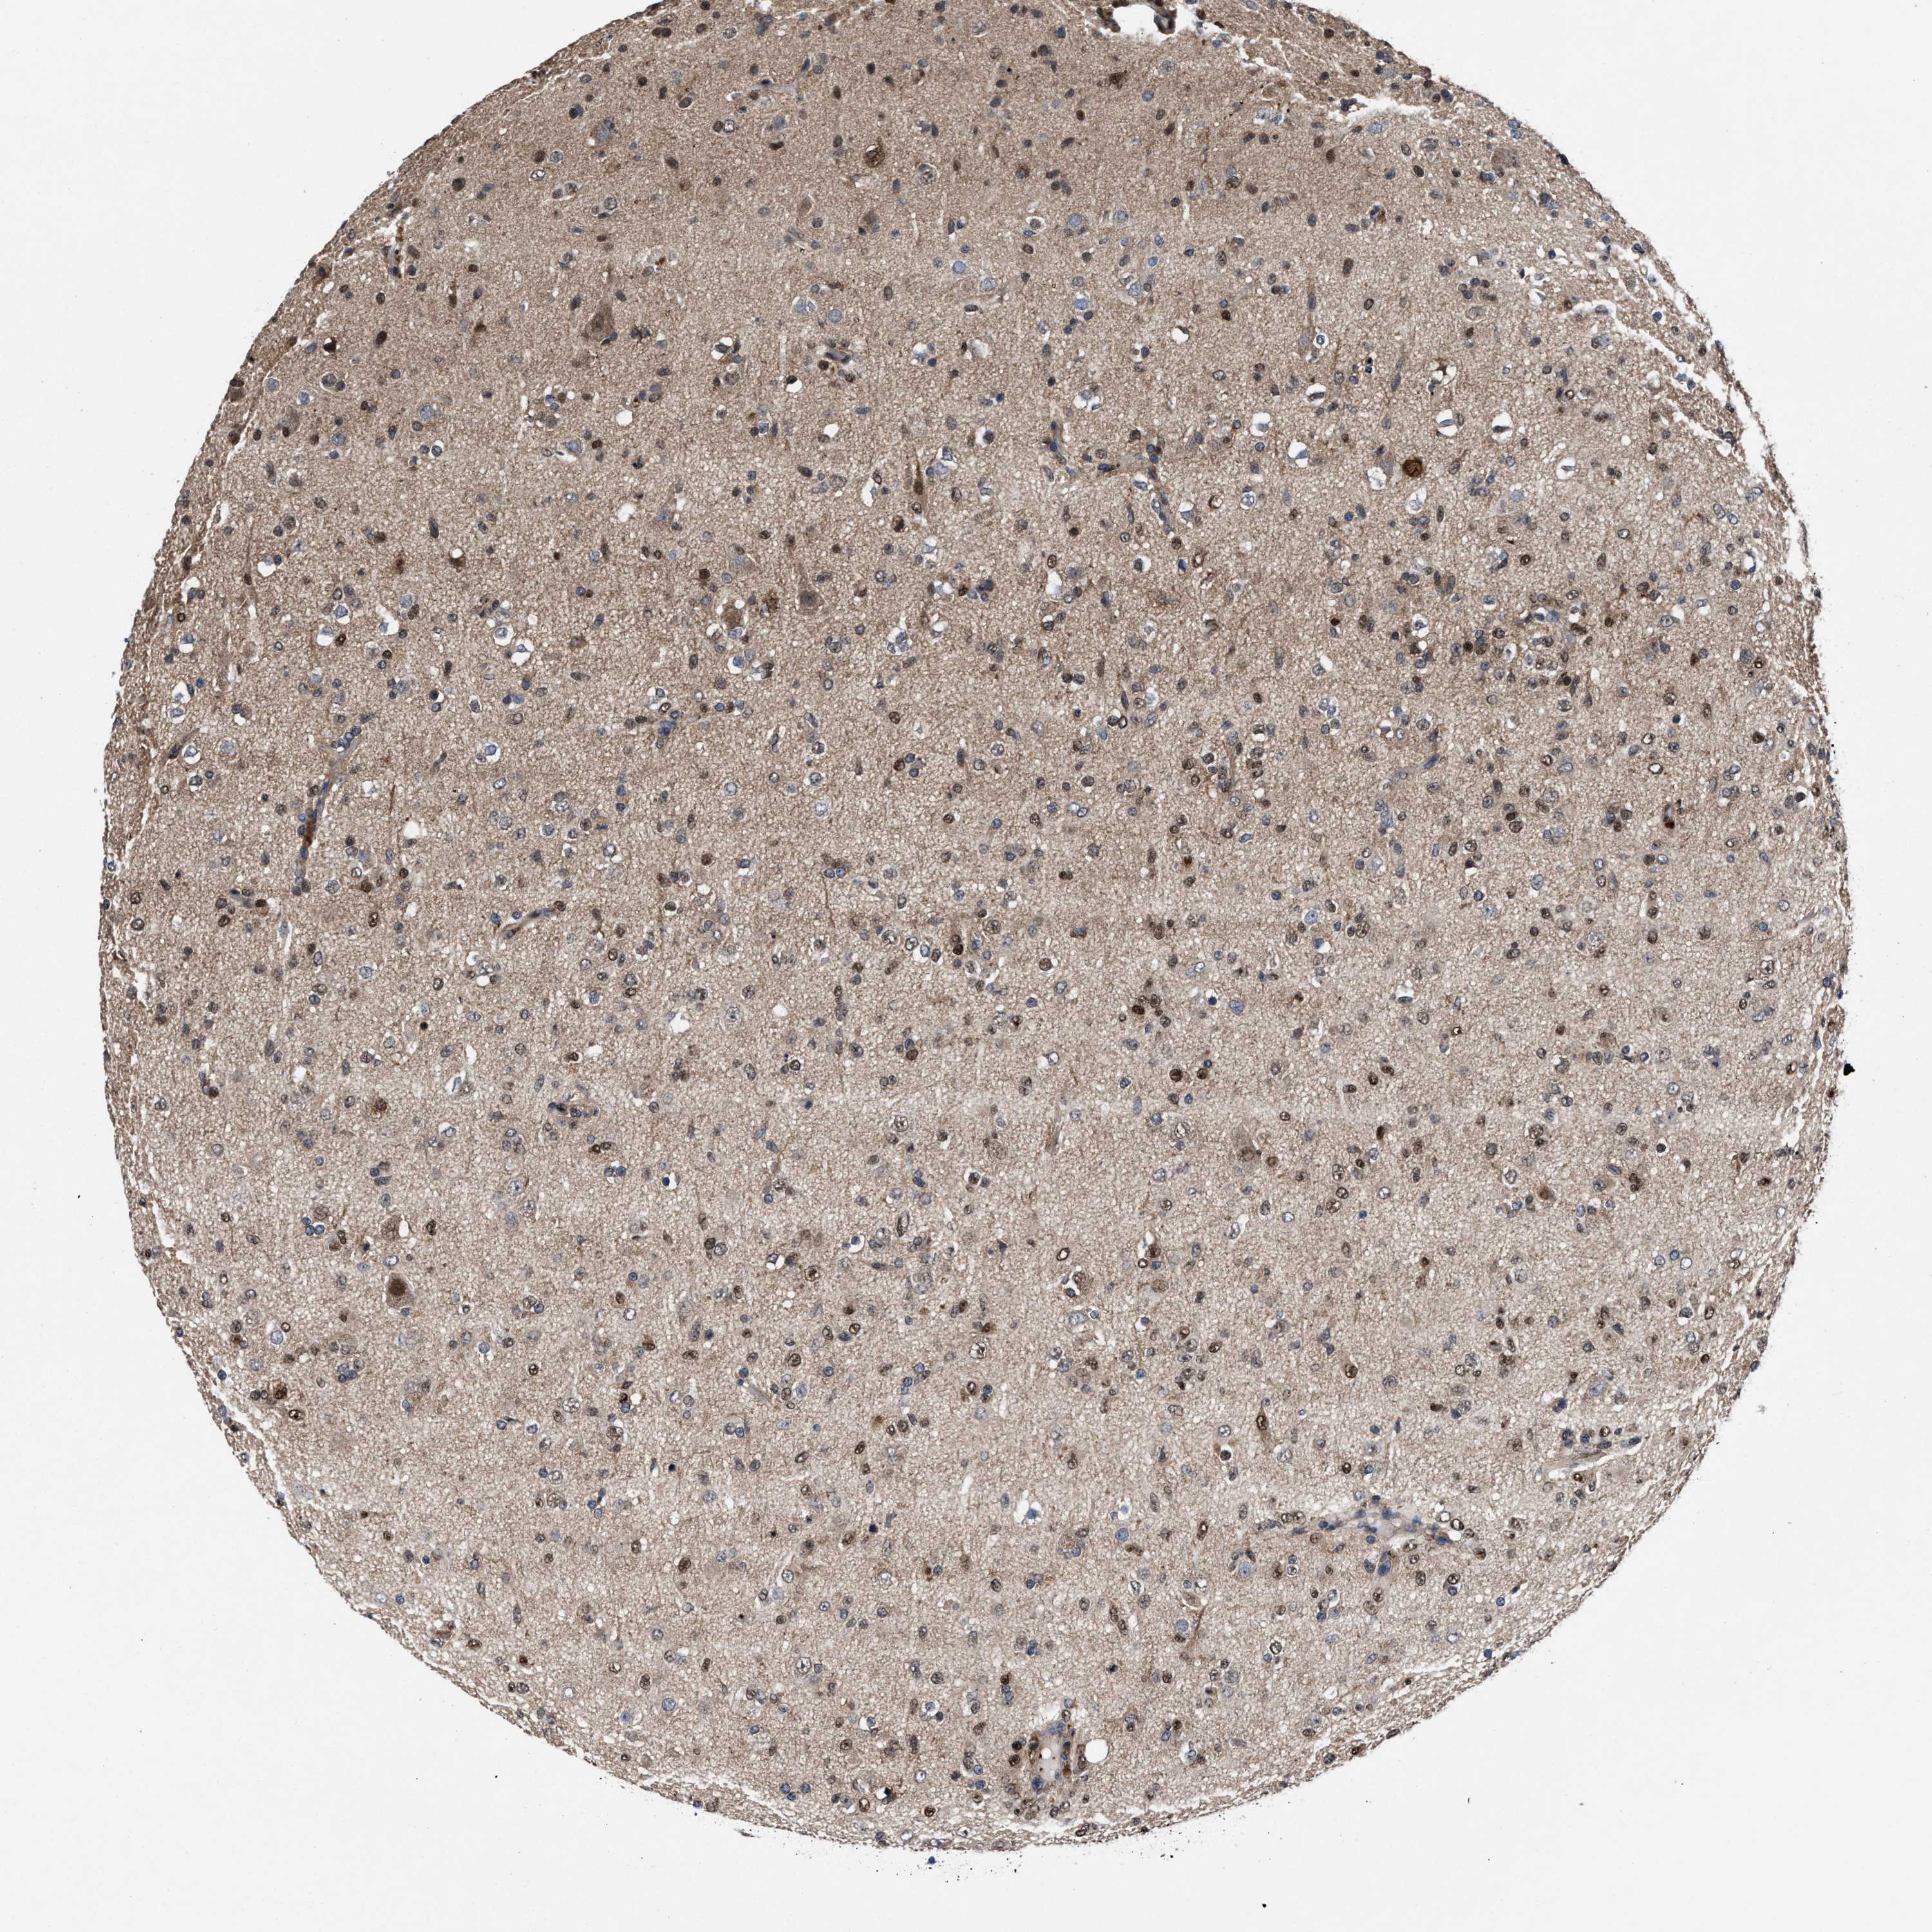

GLIOMA - Protein expressioni

A mouse-over function shows sample information and annotation data. Click on an image to view it in a full screen mode. Samples can be filtered based on level of antibody staining by selecting one or several of the following categories: high, medium, low and not detected. The assay and annotation is described here.

Note that samples used for immunohistochemistry by the Human Protein Atlas do not correspond to samples in the TCGA dataset.

Antibody stainingi

Antibody staining in the annotated cell types in the current human tissue is reported as not detected, low, medium, or high, based on conventional immunohistochemistry profiling in selected tissues. This score is based on the combination of the staining intensity and fraction of stained cells.

Each image is clickable and will lead to virtual microscopy that enables deeper exploration of all samples and also displays staining intensity scores, fraction scores and subcellular localization as well as patient and tissue information for each sample.

HPA022434

HPA022953

HPA022959

HPA028758

CAB007783

Glioma, malignant, High grade

Glioma, malignant, Low grade

Glioblastoma, NOS